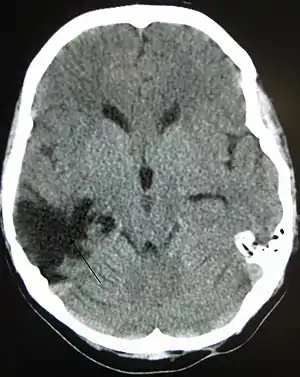

| CT scan showing cerebral contusions, hemorrhage within the hemispheres, and subdural hematoma. There is also displaced skull fracture of left transverse parietal and temporal bones.[2] | |

One type of focal injury, cerebral laceration, occurs when the tissue is cut or torn.[66] Such tearing is common in orbitofrontal cortex in particular, because of bony protrusions on the interior skull ridge above the eyes.[100] In a similar injury, cerebral contusion (bruising of brain tissue), blood is mixed among tissue.[32] In contrast, intracranial hemorrhage involves bleeding that is not mixed with tissue.[66]

Hematomas, also focal lesions, are collections of blood in or around the brain that can result from hemorrhage.[24] Intracerebral hemorrhage, with bleeding in the brain tissue itself, is an intra-axial lesion. Extra-axial lesions include epidural hematoma, subdural hematoma, subarachnoid hemorrhage, and intraventricular hemorrhage.[105] Epidural hematoma involves bleeding into the area between the skull and the dura mater, the outermost of the three membranes surrounding the brain.[24] In subdural hematoma, bleeding occurs between the dura and the arachnoid mater.[32] Subarachnoid hemorrhage involves bleeding into the space between the arachnoid membrane and the pia mater.[32] Intraventricular hemorrhage occurs when there is bleeding in the ventricles.[105]